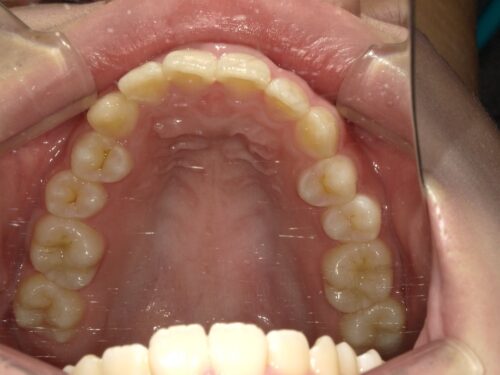

治療前・上顎の写真

上の歯並びも確認していきます。これから治療を進めていくにあたって、この状態がスタート地点になります。